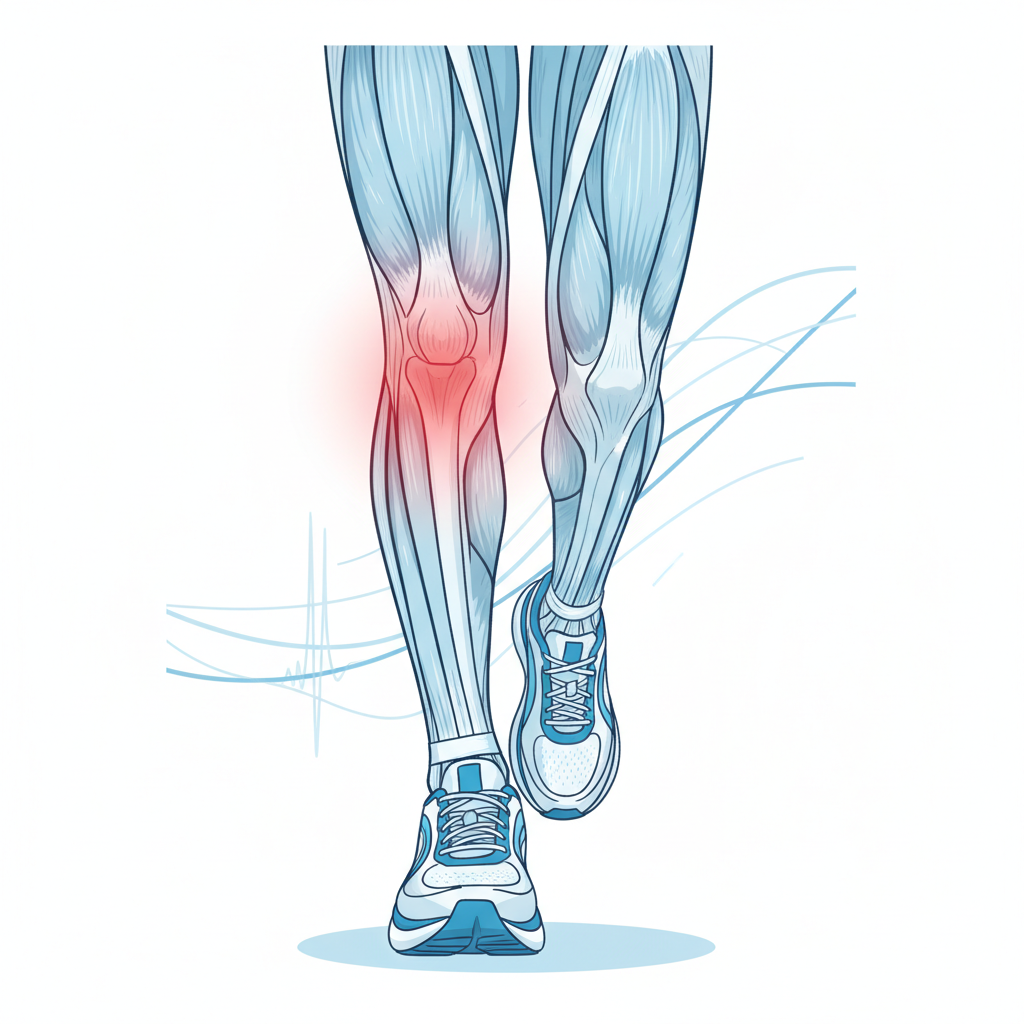

AGM Fisioterapia es la referencia en Oleiros para diagnóstico con ecografía y tratamientos invasivos mínimamente invasivos. Especializados en tendinopatías crónicas, lesiones deportivas, dolor de hombro, fascitis plantar y espolón calcáneo. Aplicamos EPI ecoguiada y ondas de choque focalizadas — técnicas que requieren formación específica y acceso a ecógrafo de alta resolución.

Tendinopatías · Lesiones deportivas · Hombro · Talón · Rodilla

| Tendinitis crónica, fascitis, espolón, dolor de hombro | AGM Fisioterapia |

| Lesión deportiva con ecografía diagnóstica | AGM Fisioterapia |